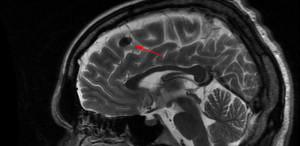

МРТ ГОЛОВНОГО МОЗГА: МНОЖЕСТВЕННЫЕ ОЧАГОВЫЕ ИЗМЕНЕНИЯ

Некротические клетки начинают постепенно погибать под давлением растущей нейроглии. После этого формируются островки глиоза различной формы, размера и местоположения. Выделяют несколько типов патологического процесса:

- Очаг сосудистого изменения, иначе именуемый периваскулярным участком. Нейроглия формирует островки, видимые на пленках КТ, вокруг атеросклеротических измененных сосудов мозга, вызывая еще большее их сдавление.

- Внутрижелудочковая форма. Очаги изменения возникают на внутренней поверхности желудочков мозга, за счет чего значительно уменьшается их объем и количество спинномозговой жидкости (такое изменение четко видно на МРТ).

- Краевая форма. Единичные простые очаги нейроглии возникают в наружной части мозговой ткани: повреждение считается одним из самых легких, потому что не затрагивает центральный участок.

- Распространенный глиоз представляет собой массивные очаговые поражения тканей. На МРТ такая картина выглядит подобно пятнистому полю.

Очаги глиоза

При легких патологических процессах не происходит нарушения функций мозга. Все очаговые изменения на МРТ можно разделить на две группы по их отображению на пленке:

- Гиперинтенсивные. Имеют более четкую и выраженную структуру, хорошо окрашиваются.

- Гиподенсные. Плохо поддаются окрашиванию, не структурированы, встречаются реже, чем гиперинтенсивные.